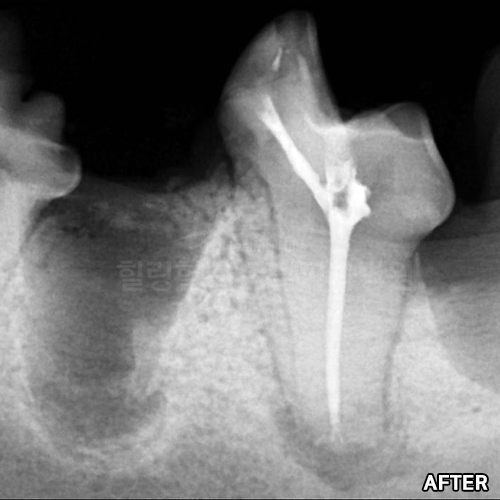

치아뿌리까지 파절된 강아지어금니 빨갛게 부어오른 잇몸치료~ 2년 뒤에 재생된 잇몸뼈 CT로 확인! 모든 동물병원에서 발치하자고 했지만 힐링힐스동물치과병원에서 되살려진 어금니!